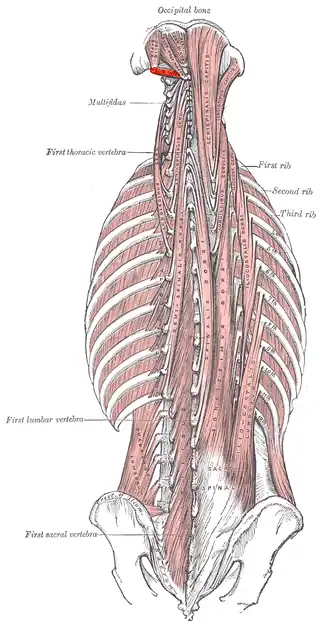

Deep muscles of the back. (Obliq. infer. labeled at upper left.) | |